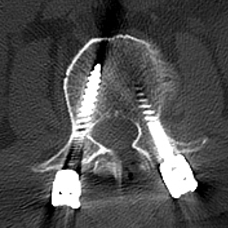

64岁的邱某因“腰痛多年,加重伴左下肢放射痛1月”来到昆山市中医医院脊柱骨科陈勇主任门诊就诊,经对患者的评估后,陈勇主任考虑其为“腰椎间盘突出症、腰椎椎管狭窄症”,随即安排住院治疗。

入院后,陈勇主任在科室组织了病例讨论并表示:常规保守治疗只能缓解症状无法从根本上解决病根。目前,患者已保守治疗1月,症状未见明显缓解,且进行性加重。影像学可见腰椎间盘突出伴椎管狭窄严重程度高,有明确的手术指征,结合患者及其家属的意愿,选择腰椎后路减压植骨融合内固定术。

▲术前MRI